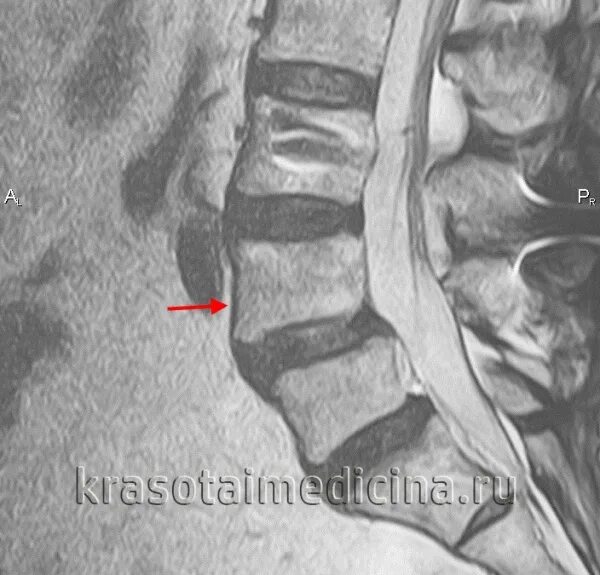

Смещение позвонков поясничного операция